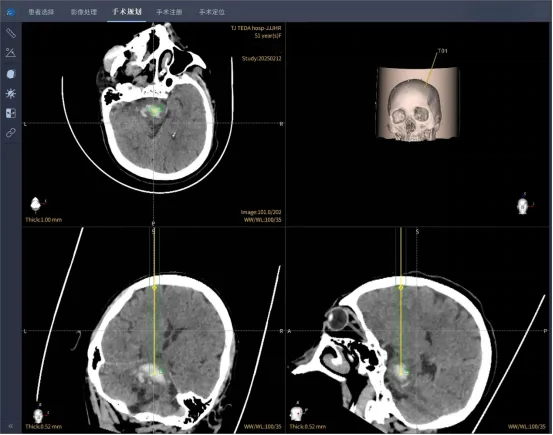

为挽救患者生命,同时改善患者功能预后,泰达医院神经外科立即为患者进行了机器人脑干血肿穿刺抽吸术。专家团队迅速制定手术计划,手术前应用计算机进行精确的手术路径设计,避开重要神经功能区及血管,以最小的创伤及路径,达到彻底清除血肿的目的。

在机器人导航定位下,一根长约10cm引流管的头端精确放置于脑干出血的中心位置,并抽出2ml颅内血肿,减轻了血肿对脑干组织的压迫及损伤。